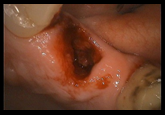

抜歯した歯

まずこの歯を抜歯し、きれいに処置して破折部分を特別なセメントで接着します。接着面の処置を行い、再び抜歯窩に戻し固定します。